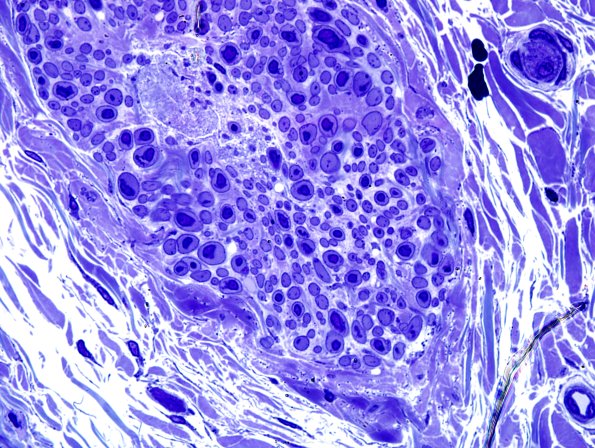

The plastic sections of one vessel show an unusual proliferation of discohesive smooth muscle cells. (plastic section)